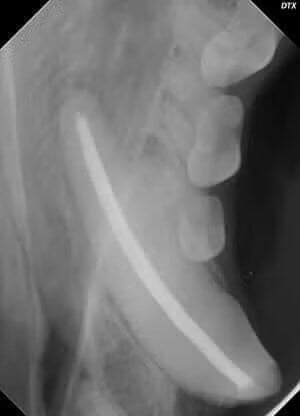

Any chipped or discolored tooth may have a root canal (endodontic) problem. They are usually diagnosed on the physical exam after the heavy tartar is removed and when an abscess is seen at the tip or apex of the tooth on a radiograph.

A root canal causes less trauma to the surrounding bone and soft tissues, is less painful than an extraction, and the function of the tooth is often preserved. We especially consider root canals for the more important teeth in the mouth, such as the canine teeth and large premolars and molars. There are many teeth in dogs and cats that are too small to be good candidates for a root canal. In these cases, extraction of the tooth would be the best option.